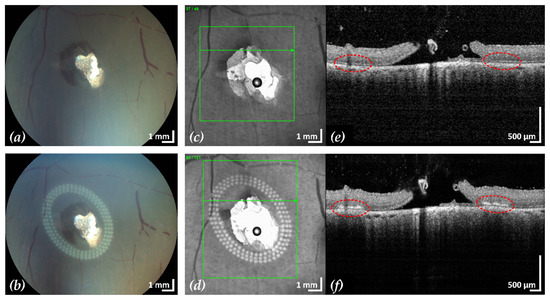

Figure 5. Example 2: treatment outcome in ex-vivo porcine eye with artificially induced retinal break (area of retinal break and adjacent RD: 15.4 mm2). Fundus photographs before (a) and after (b) treatment, infrared scanning laser ophthalmoscope images before (c) and after (d) treatment with the corresponding SD-OCT B-scans (e,f). A total of 153 lesions were applied in three rows with a radial and tangential (point to point) distance of 200 µm and 300 µm, respectively. The LPC treatment time was 2:11 min. The effect of LPC treatment is visible in (b,d) as spots of whitened tissue and in (f) as ruptures in the retina at the treatment sites (red).

After treatment, CFP and cSLO showed the typical tissue whitening caused by LPC lesions around the retinal break (Figure 3). The SD-OCT B-scans showed hyperreflectivity of the retina at the laser application sites, indicating successful treatment. In most eyes, the laser treatment was entirely applied in regions of still attached NSR, the goal of successful laser retinopexy to seal the break. Two exemplary results are shown in Figure 4 and Figure 5.